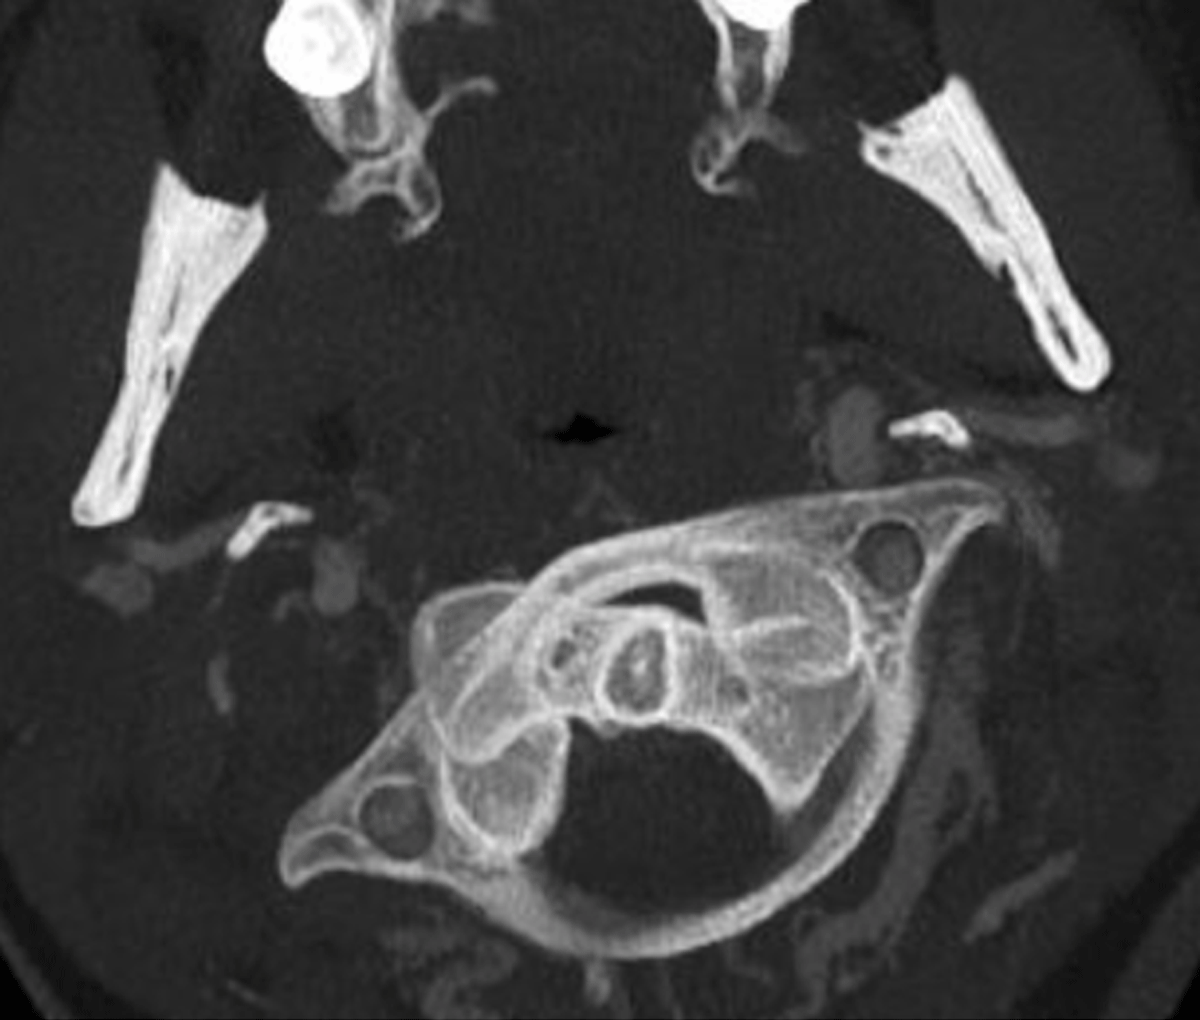

A 19-year-old female presented to the emergency department for neck pain and stiffness of two weeks duration following a sharp neck movement. Axial 15-mm-thick maximum intensity projection of cervical spine CT suggested the diagnosis of Fielding type I AARF on the basis of rotation of C1 on C2 (Figure 1). The patient was discharged. Persistent neck pain led to re-admission. Magnetic resonance imaging (MRI) evidenced exclusive C1–C2 rotation. A ‘dynamic’ CT with maximal left-sided head rotation confirmed the fixed character of the C1–C2 complex as they rotated as a unit (Figure 2).

Figure 1

Rotation of C1 on C2 on CT in neutral position.